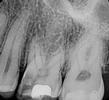

Our Vienna, VA dentists plan treatment using a digital x-ray image of the tooth. We may also recommend a 3-D digital scan of the tooth using CT cone beam technology. This valuable technology provides more information than a two-dimensional x-ray and allows for more precise treatment planning.

When we begin your root canal treatment, we first open a small hole in your tooth to access the root canal. Dr. Sanati and Dr. Sharahm use leading-edge rotary endodontic technology to gently and quickly remove the infected material. Instead of the manual steel files dentists used in the past, rotary endodontics employs an electrically-powered instrument that allows us to perform more efficient and comfortable root canals with a higher success rate for our patients.

When our Tysons dentists have cleared away every trace of the infection, they fill the hollowed-out space with an inert material called gutta-percha and then seal the tooth. Since there is no more blood supplying the tooth, it will become brittle, so we may recommend a dental crown to protect it. If you don't need a dental crown, we will still need to place a filling on the tooth to restore and strengthen it.